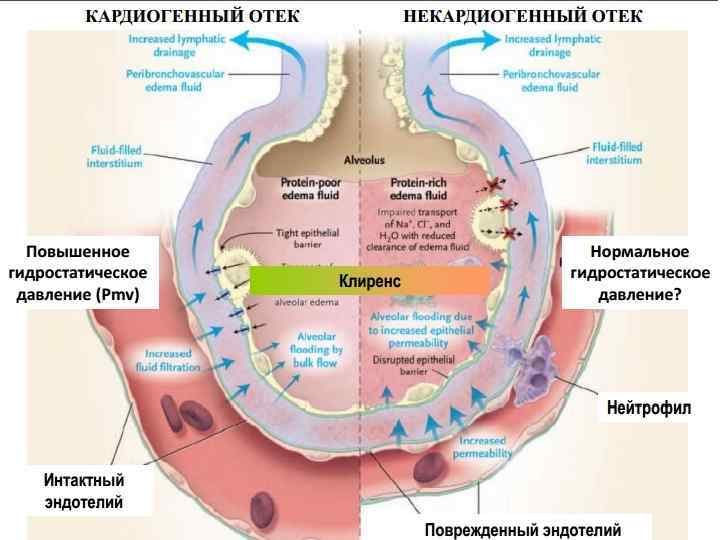

Классификация • Кардиогенный (гидростатический, гидравлический) • Некардиогенный (синоним ОРДС)- тоже гидростатический за счет роста легочного венозного сопротивления • Смешанный (гемодинамическое повреждение легких. Например, вентилятор-индуцированный отек) • Неясная этиология – гепатопульмональный синдром – постпневмонэктомический синдром – посттрансплантационный – реперфузионный и т. д.

Классификация • Кардиогенный (гидростатический, гидравлический) • Некардиогенный (синоним ОРДС)- тоже гидростатический за счет роста легочного венозного сопротивления • Смешанный (гемодинамическое повреждение легких. Например, вентилятор-индуцированный отек) • Неясная этиология – гепатопульмональный синдром – постпневмонэктомический синдром – посттрансплантационный – реперфузионный и т. д.

Механизмы Основные механизмы : • Рост гидростатического давления (легочные вены и капилляры) • Проницаемость эндотелия • Персистирующая легочная вазодилатация – “shear stress” – отслойка эндотелия • Реперфузия (интенсивная терапия шока) или избыточная инфузия

Механизмы Основные механизмы : • Рост гидростатического давления (легочные вены и капилляры) • Проницаемость эндотелия • Персистирующая легочная вазодилатация – “shear stress” – отслойка эндотелия • Реперфузия (интенсивная терапия шока) или избыточная инфузия